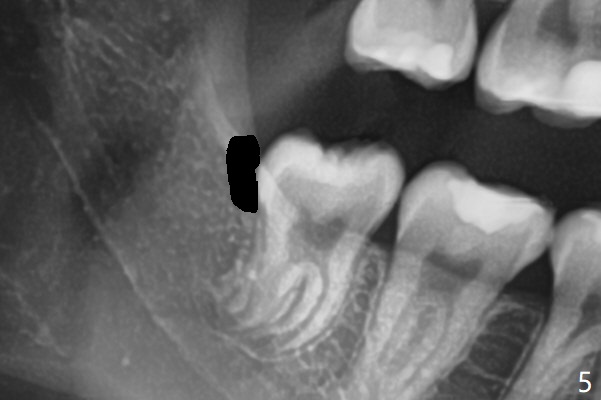

19岁女抱怨右下智齿远中龈下食物坎塞,不希望拔除,因为缺牙太多:先天性缺失一个下切牙,为了矫正又拔除4个双尖牙(图一)。临床检查32号牙远中牙龈覆盖(图二:*),而17号牙萌出不多(图三),没有食物坎塞史。局麻下,使用Diode Laser (Picasso)切除牙龈直到智齿远中咬合面暴露(图四)。术后突然意识到为了防止牙龈重新覆盖,必须做crown lengthening,也就是切除远中骨质(图五(黑色),与图一’对比),是吗?随访时利用Shining口扫记录,拍摄角度好。